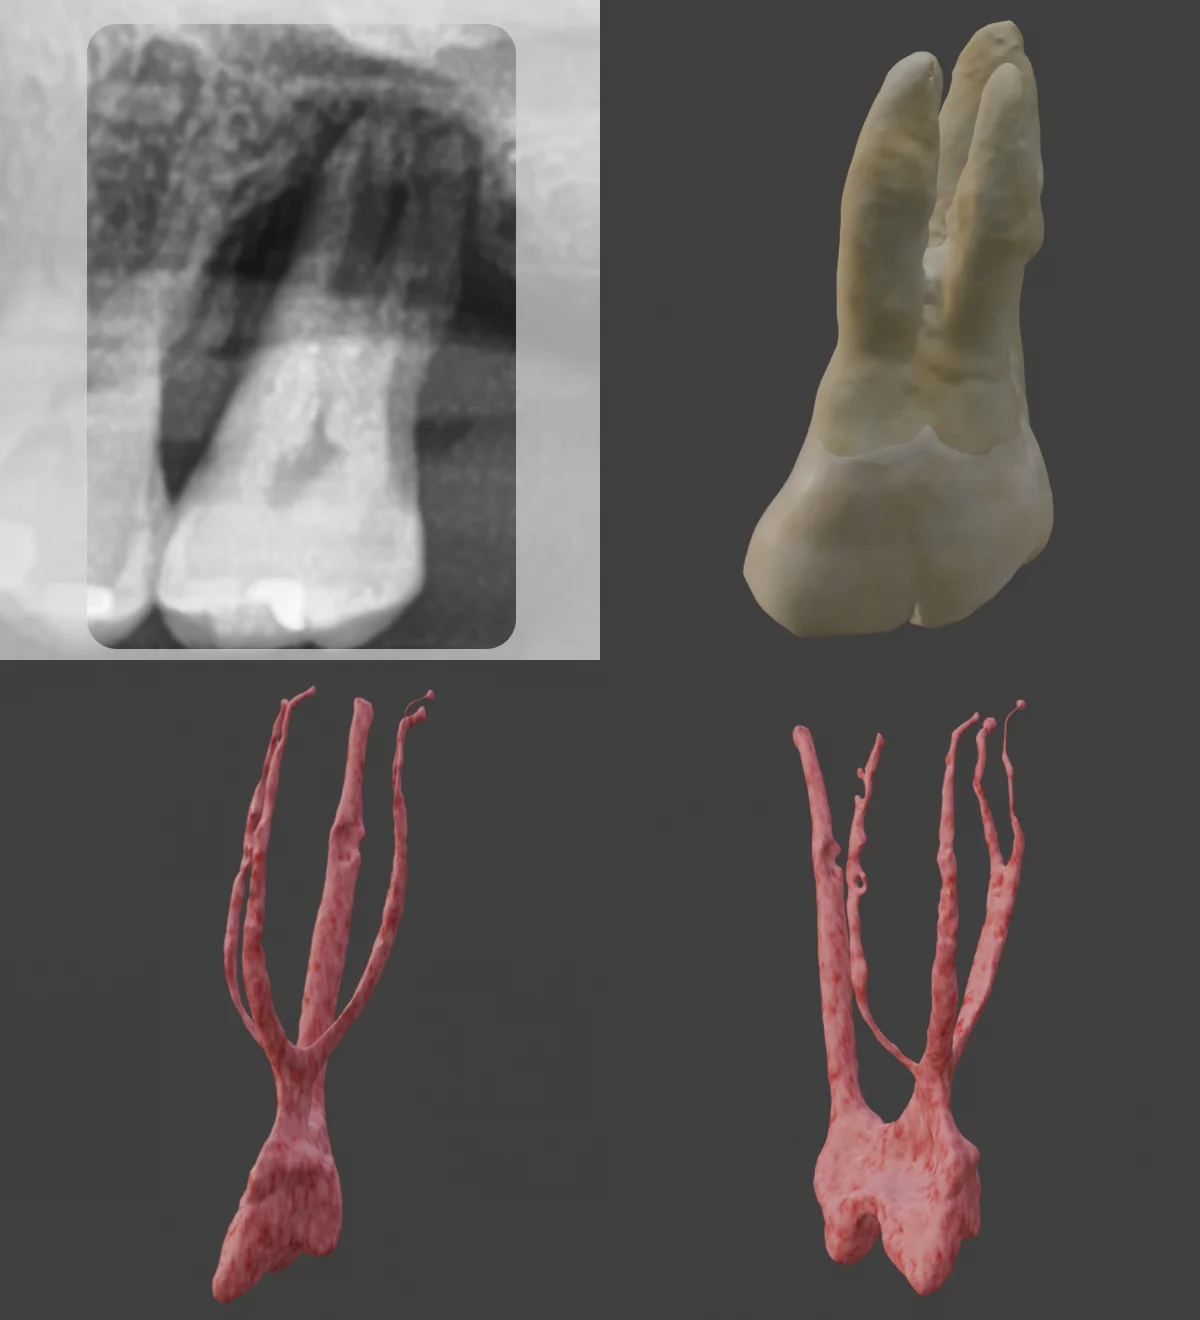

🔹 Single Buccal Orifice Splitting into Three Canals

Check out the X-ray on this case! You’ll see a single buccal orifice that then splits into MB, MB2, and DB canals. Clinically, this could be a nightmare if unprepared! But with Dental EndoMaster, you can train on similar cases, making the real thing much easier to tackle. 😎